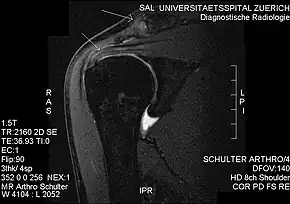

MRI showing subacromial impingement with partial rupture of the supraspinatus tendon, but no retraction or fatty degeneration of the supraspinatus muscle.

Impingement syndrome can be diagnosed by a targeted medical history and physical examination,[11][12] but it has also been argued that at least medical imaging[13] (generally X-ray initially) and/or response to local anesthetic injection[14] is necessary for workup. However, imaging studies are unable to show cause of shoulder pain in diagnosing. For example, MRI imaging would show rotator cuff pathology and bursitis but is unable to specify the cause.[15]